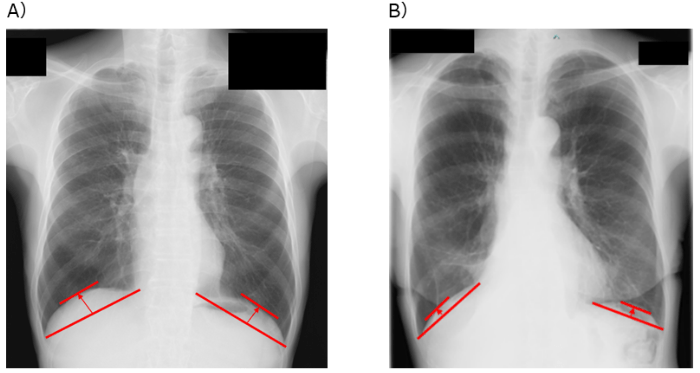

そこで研究グループは、胸部X線画像から簡便に測定できる横隔膜の位置の高さである「横隔膜ドーム高※3」という指標に注目しました。横隔膜ドーム高は、肺機能や運動耐容能と密接に関連することが明らかになっており、より簡便かつ患者に負担なく術後予後を予測する指標となる可能性があります。しかし、これまで肺がん患者において、横隔膜ドーム高と術後の予後との関連性は明らかにされていませんでした。

研究グループは、近畿大学病院において肺がんの肺葉切除術を受けた患者を対象に、術前1カ月以内に撮影された胸部X線画像を用い、肺腫瘍側の横隔膜ドーム高を測定しました。その結果、多変量解析※5 において、術前の横隔膜ドーム高は術後予後に影響を及ぼすことが知られている喫煙状況、肺機能、がんのステージなどの因子の影響を受けず、独立した術後予後を予測できる因子であることが明らかとなりました(HR=2.10、p<0.01)。さらに、時間経過に伴う生存率の推移を示すカプラン・マイヤー生存曲線※6 による解析では、横隔膜ドーム高が低い患者群において、3年間の全生存率※7 が有意に低く(p<0.01)、加えて肺炎や呼吸不全などの呼吸器疾患による死亡に限定した場合でも、3年の疾患特異的生存率※8 が有意に低いことが示されました(p<0.01)。これらの結果から、横隔膜ドーム高が低い患者群に対する術前呼吸リハビリテーションは、術後予後改善へ向けて重要である可能性が示唆されました。

※3 横隔膜ドーム高:横隔膜がどれくらい上に持ち上がっているか(高さ)を示す指標。

※6 カプラン・マイヤー生存曲線:時間の経過ごとの生存率を可視化する統計手法。